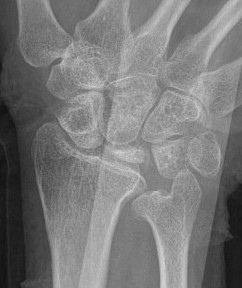

Xray

Progressive changes of AVN

- sclerosis

- fragmentation / fracture / flattenging

- midcarpal collapse: scaphoid flexion / capitate descent

- radiocarpal and midcarpal osteoarthritis

Lichtmann Classification

| Stage II | Stage IIIA |

| Sclerosis |

Collapse / fragmentation Normal carpal height |